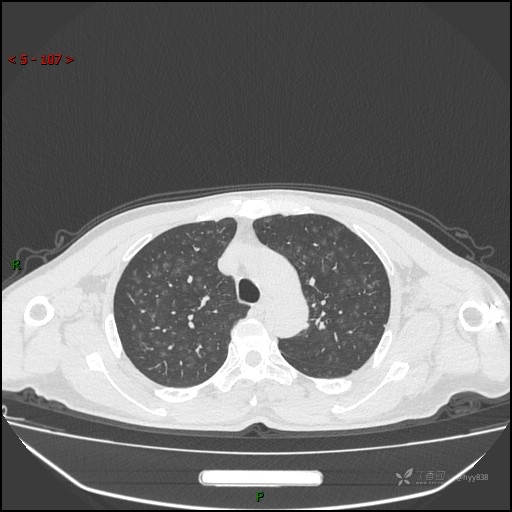

呼吸科电话会诊病例:过敏性肺炎 VS 吸烟相关间质性肺炎 VS 尘肺……结果公布~

性别:男

年龄:55岁

简要病史:渐进性呼吸困难。

胸部CT平扫

电焊工尘肺 (2)